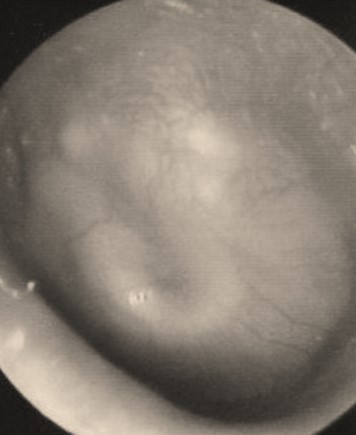

Voici des photographies réalisées lors de votre consultation :

Joshua ne marche pas encore. Son vocabulaire est limité à quelques sons, il ne répète pas de syllabes, n’appelle pas encore « maman » ni « papa ».

Inquiets par le retard de langage de Joshua, vous réalisez l’examen suivant :

En rose : conduction aérienne

En bleu : conduction osseuse

Les résultats de cet examen sont superposables pour l’oreille gauche et l’oreille droite.

Question 15: Joshua

Il existe un risque de surdité suite à une méningite bactérienne. Celle-ci peut apparaître très précocement. Il en est de même du risque d’ossification cochléaire.

Le bilan auditif doit donc être réalisé tôt (en général 15 jours après le début de la méningite) et répété régulièrement pendant plusieurs années. En cas de surdité sévère ou profonde bilatérale, l’imagerie des rochers doit être réalisée rapidement afin de rechercher une ossification cochléaire.